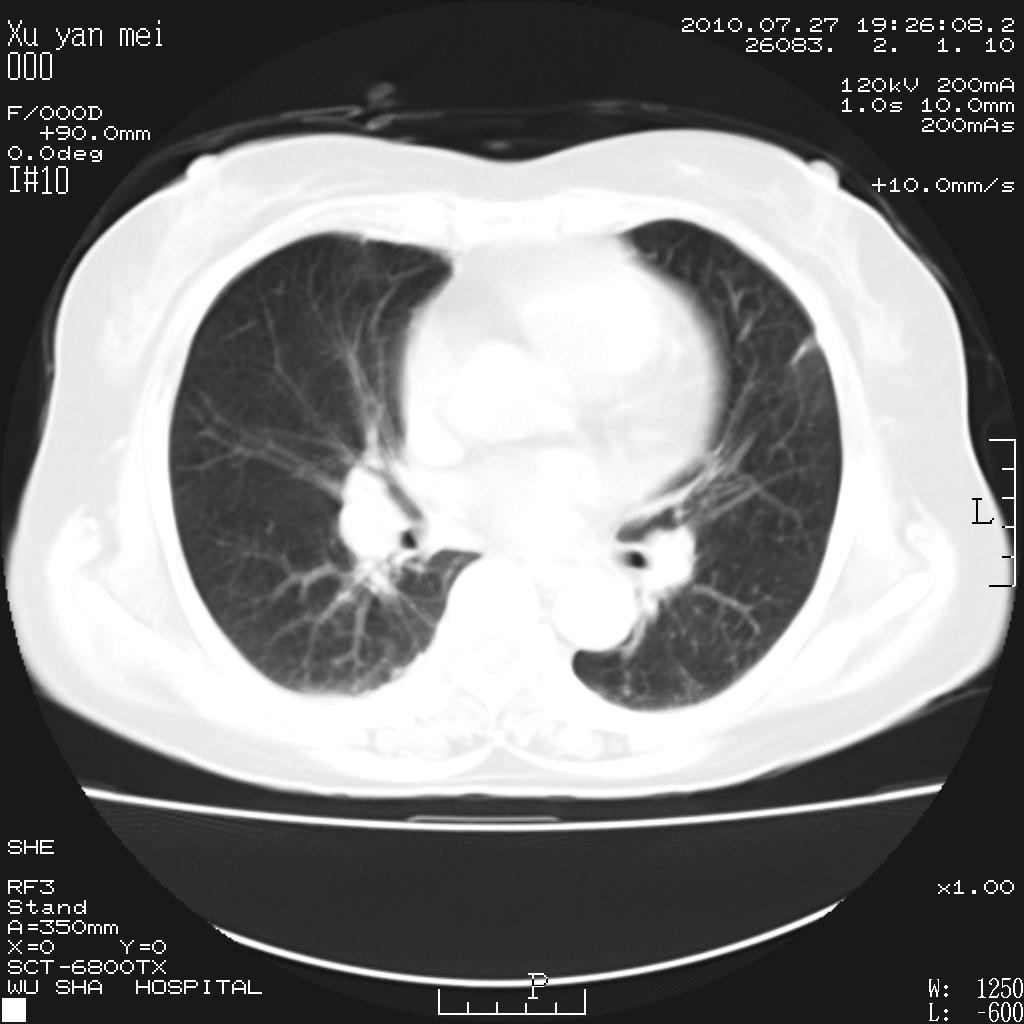

女,60岁,胸痛就诊,右肺结核?炎症?其它?(胸片右侧中上肺野确实看不到什么啊)

1)考虑两肺感染性病变;建议抗炎治疗后复查。2)双侧少量胸腔积液。

1)考虑两肺感染性病变;建议抗炎治疗后复查。2)右侧少量胸腔积液。

双肺炎症可能性大,建议抗炎后复查。右侧胸腔少量积液。双侧胸膜轻度增厚。

考虑两肺感染性病变;不除外肺栓;建议抗炎治疗后复查。